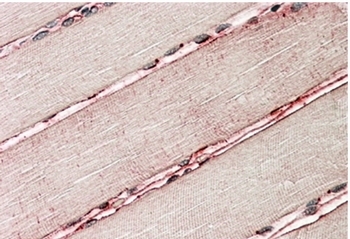

Supportive validation

- Submitted by

- Acris Antibodies GmbH (provider)

- Main image

- Experimental details

- AP32139PU-N Delta-Sarcoglycan staining of paraffin embedded Human Skeletal Muscle at 3.8 µg/ml. Steamed antigen retrieval with citrate buffer pH 6, AP-staining.